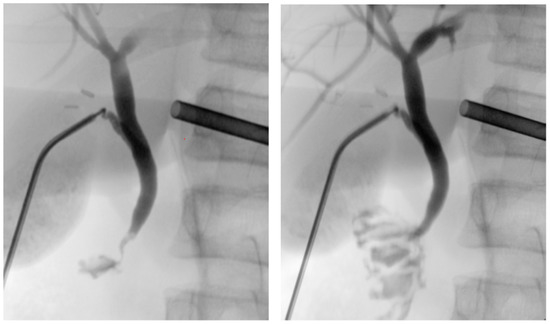

The patient was placed in a reverse Trendelenburg position, and the cholangiography was performed using fluoroscopy for dynamic visualization of the biliary tree. This showed the intrahepatic bile ducts as well as the common bile duct without dilatation and a free passage of the contrast medium into the duodenum. During irrigation of the common bile duct with normal saline serum, a small stone in the common bile duct could easily be flushed out (Figure 3). After extraction of the cholangiography kit, the cystic duct was closed by placing two clips on the permanent side and then divided. There was no intraoperative bile leak.

Figure 3. Cholangiography before and after flushing out a small stone in the common bile duct.